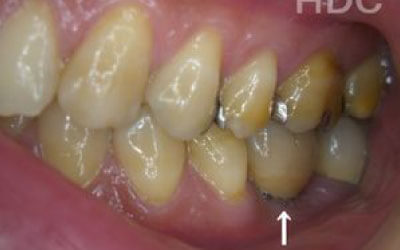

最も大きな違いは、前後の歯の寿命が変わることです。

ブリッジは、抜けた部分の前後の歯を大きな虫歯と同じくらい削る必要があります。

さらに、抜けた歯の力を前後の歯が負担するため、ブリッジを支える歯には常に1.5倍の力がかかります。

1)ブリッジ

2)歯を大きく削る+支えの歯に1.5倍の力がかかる

3)前後の歯の寿命が著しく減る

ブリッジの支えの歯は、データでは10年以内に68%が抜歯になります。